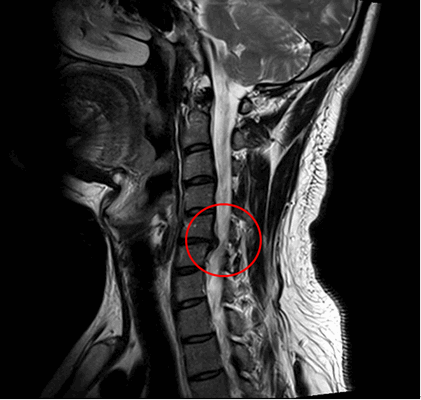

При данном заболевании с самого начала необходимо исключить наличие повреждения нервных корешков и шейного отдела позвоночника. Это означает, что в особенности при повторном наступлении болезни врачи-специалисты Геленк-Клиники используют полный спектр клинических, радиологических и неврологических методов диагностики. Кроме тщательного медицинского осмотра пациента, к таким методикам относится еще и электромиография (ЭМГ), а также МРТ.

Операции рекомендуют проводить вслучае значительных ограничений качества жизни, болезненности, нарушений чувствительности и паралича. Клиническими аспектами, являющимися главными индикаторами операции, являются дефициты неврологического характера (онемение, парез, мурашки) и др. В некоторых случаях операции нужно проводить как можно раньше, чтобы иметь возможность провести имплантацию эндопротеза межпозвонкового диска, который поможет снизить давление на спинной мозг шейного отдела позвоночника.